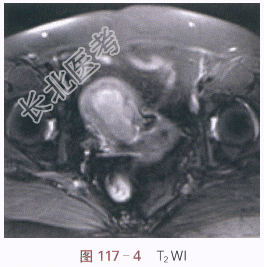

影像学资料如图117-1~图117-5所示。

读片分析:子宫稍增大,内膜弥漫性增厚,结合带中断。增强扫描后,增厚的内膜呈不规则强化,局部浸润超过肌层1/2厚度。